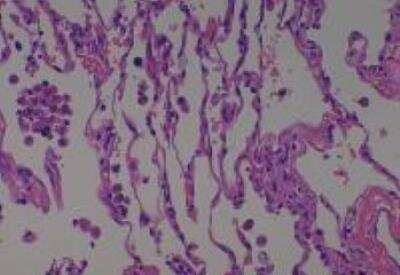

Hematoxylin & Eosin Stain: Human Common Tissue MicroArray (Normal Adjacent) [NBP2-30215] - 102. Stomach